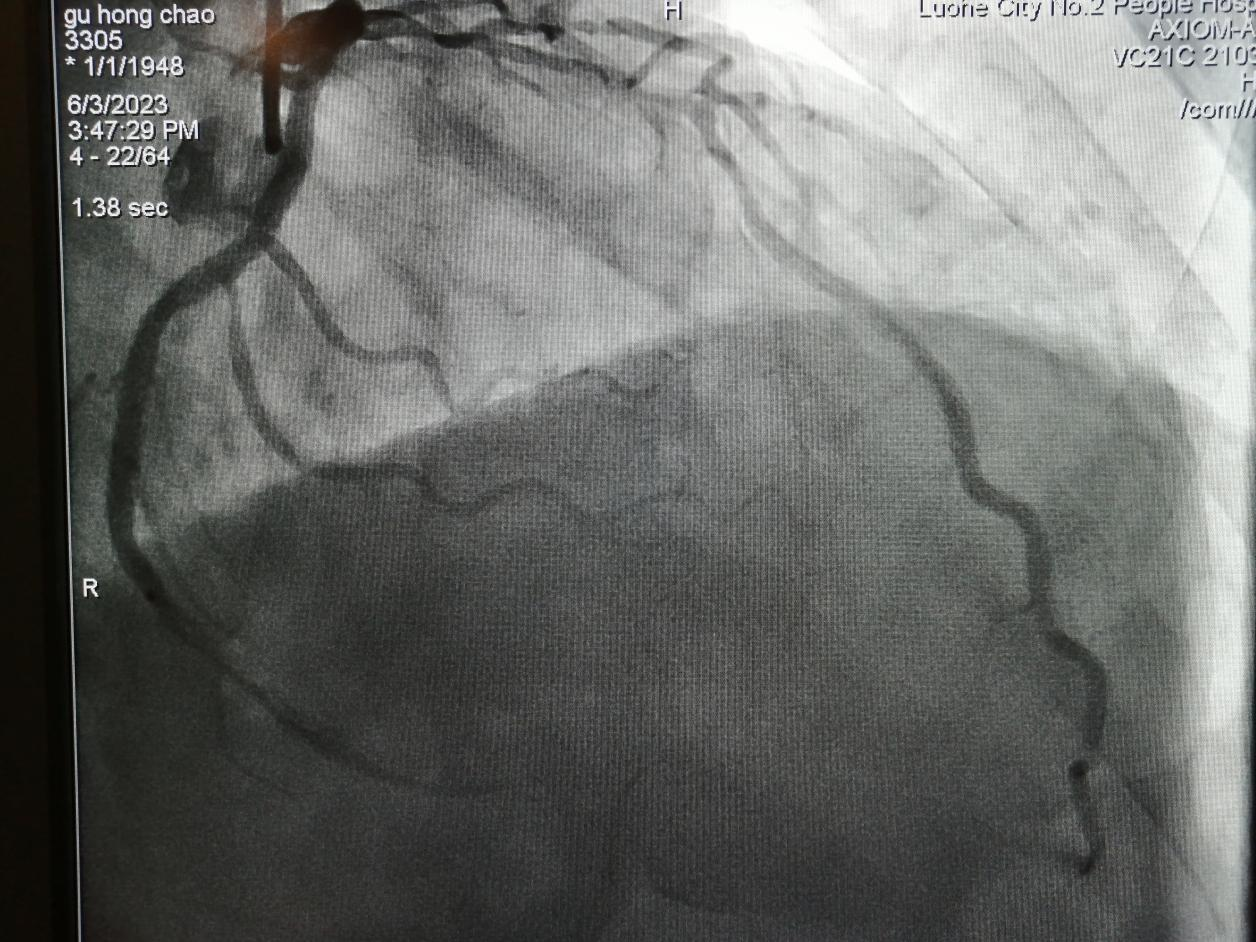

術(shù)后:

術(shù)后,谷大爺胸痛癥狀得到有效緩解。

金叔宣教授帶領(lǐng)心血管內(nèi)科介入團(tuán)隊(duì)為谷大爺制定了個(gè)體化的手術(shù)治療方案,即行血管內(nèi)超聲,旋磨前降支,后置入心臟支架1枚。